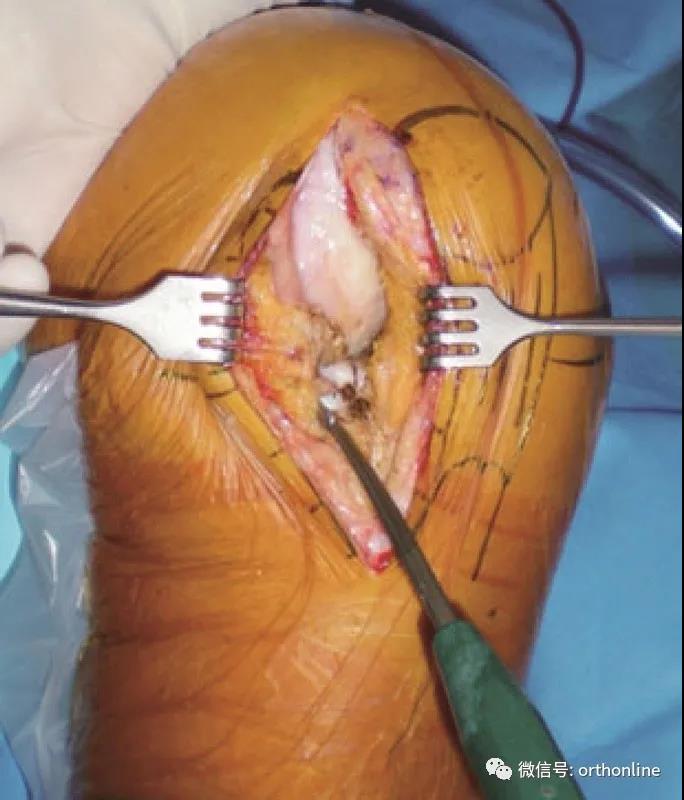

放置股骨截骨模板

股骨截骨模板放置在股骨外髁中心并垂直于胫骨截面